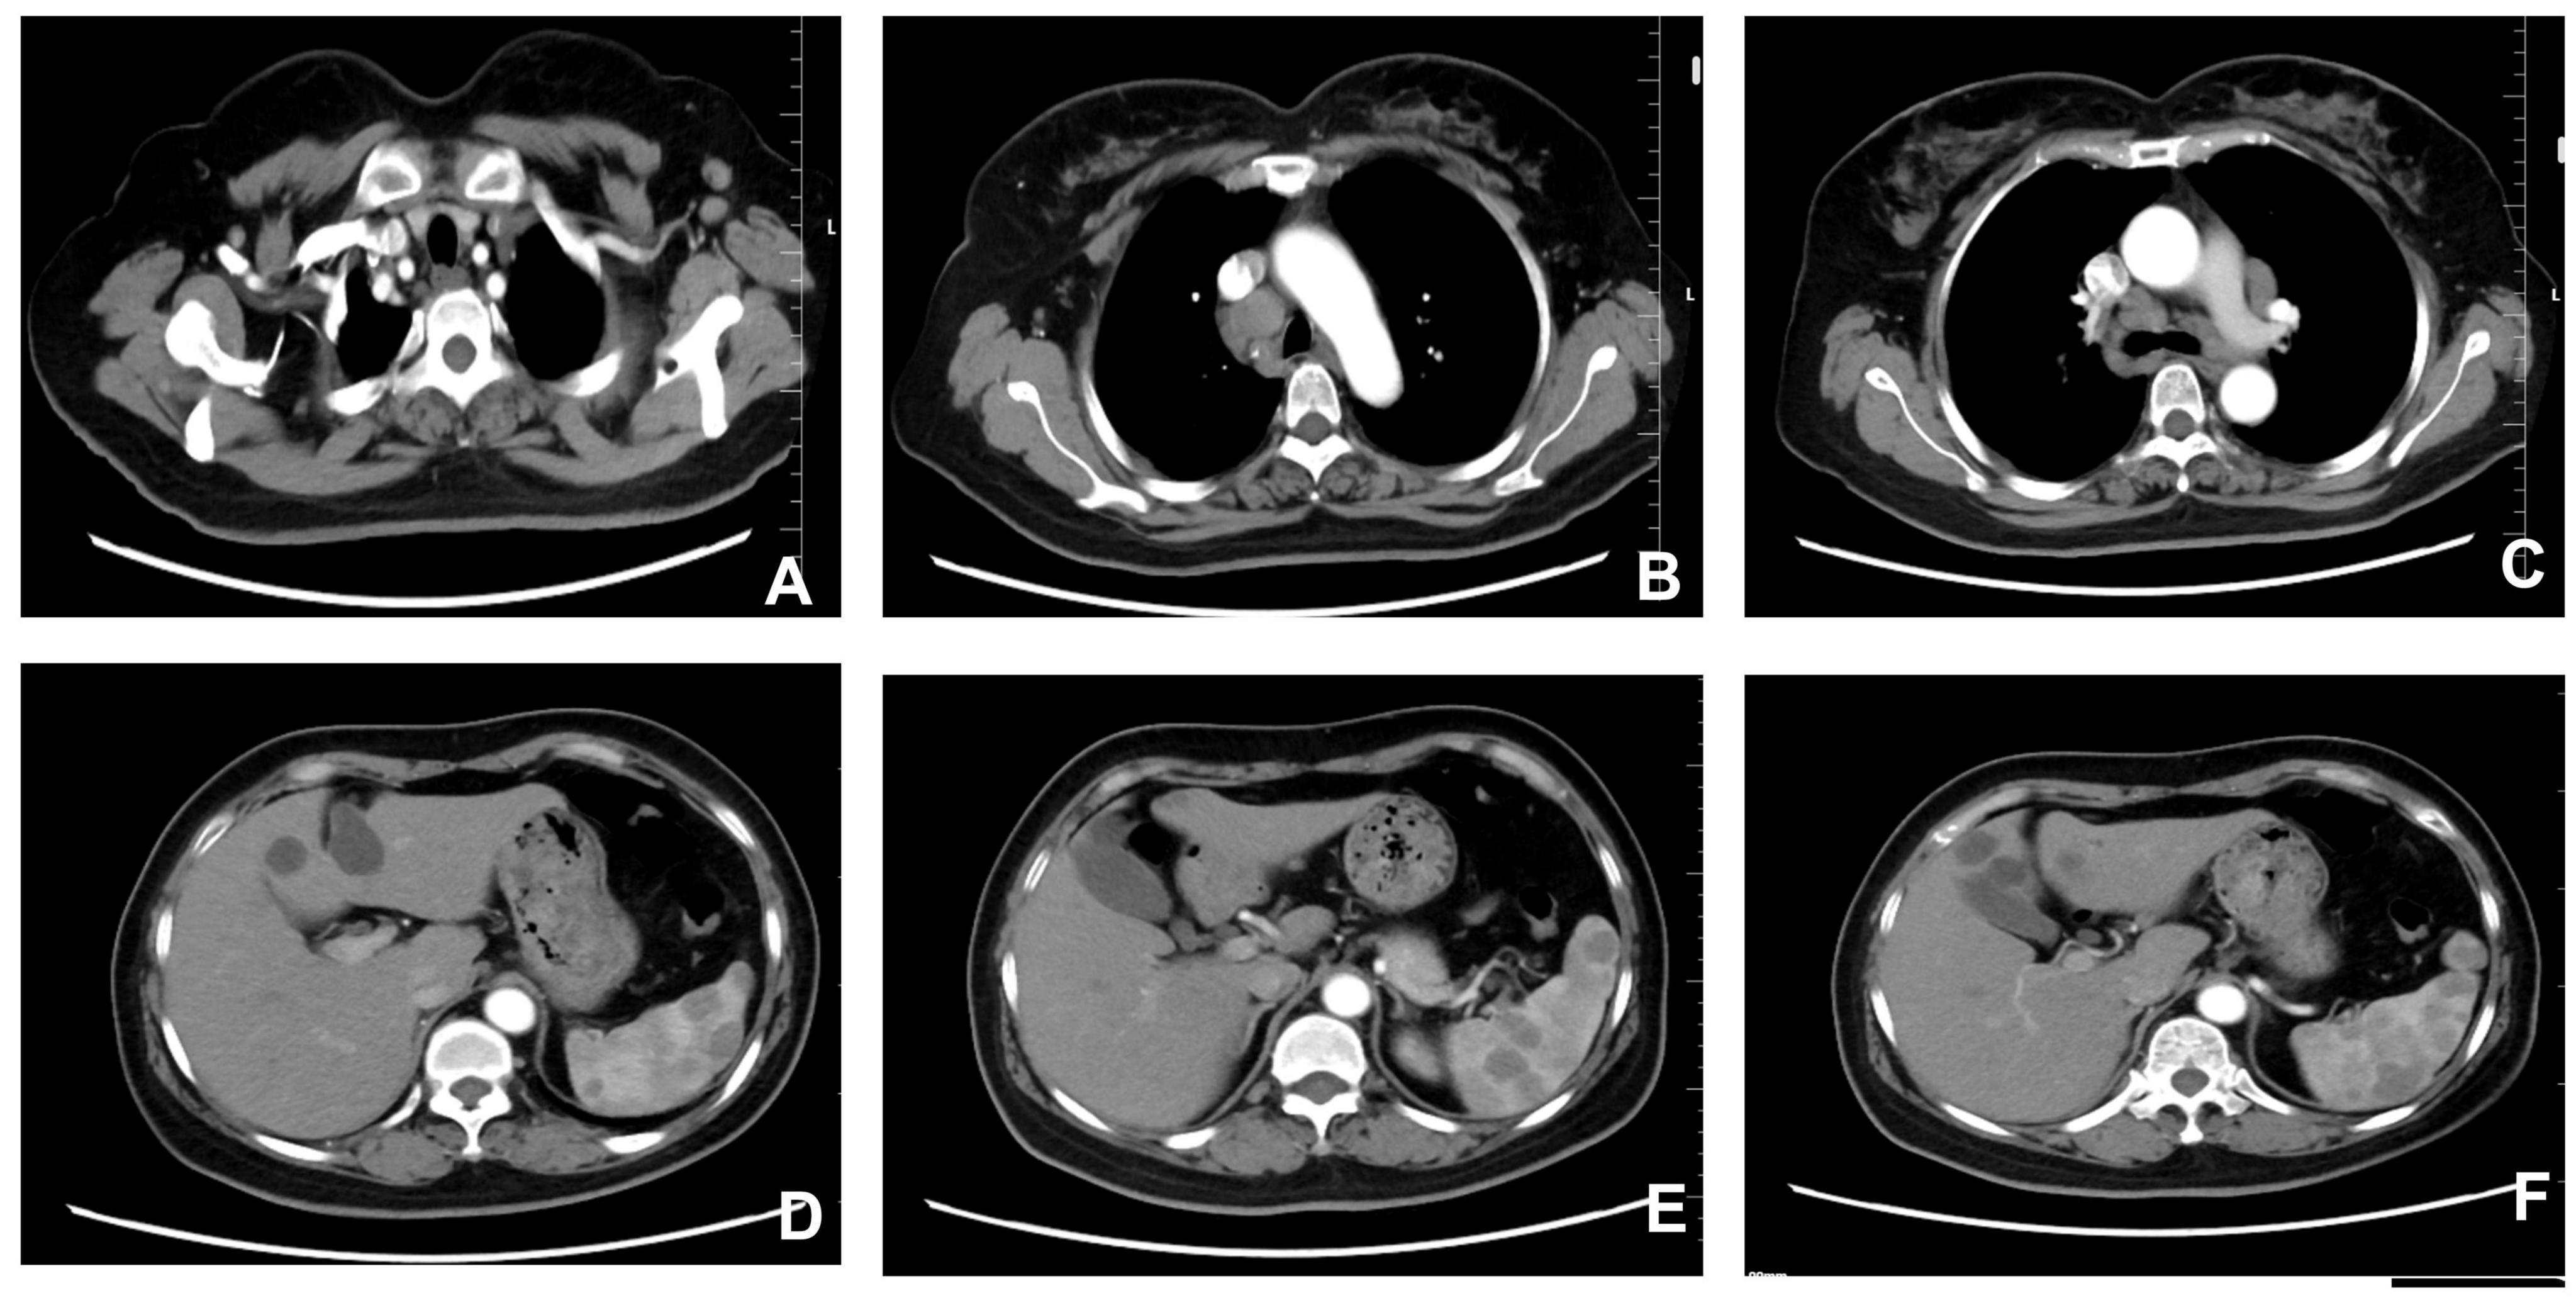

A 53-year-old female farmer presented at our hospital on September 25, 2024, with a primary complaint of “multiple enlarged lymph nodes and a splenic mass detected during a routine health check-up over the past 20 days.” Enhanced chest and upper abdominal computed tomography demonstrated multiple enlarged lymph nodes involving the mediastinum, bilateral axillary regions, cardiophrenic angles, hepatic hilum, and gastrohepatic ligament, which together raised a strong suspicion for lymphoma. In addition, several hypodense splenic nodules were identified, ranging from a few millimeters to approximately 1 cm in diameter, relatively well-defined, and showing no obvious post-contrast enhancement, features suggestive of diffuse splenic involvement. Pulmonary CT further revealed uneven parenchymal transparency accompanied by fibrous streaks in the right middle lobe, findings consistent with small airway disease and chronic inflammatory changes. Moreover, a small nodule was observed in the upper outer quadrant of the left breast, requiring further evaluation to exclude malignancy. Abdominal imaging also demonstrated mild fatty infiltration of the liver, multiple hepatic nodules radiologically consistent with cysts, and slight thickening at the left adrenal junction, providing a more comprehensive assessment of thoracoabdominal involvement (Figure 1).

FIGURE 1

Chest and upper abdominal CT. (A) Thoracic inlet level. (B) Aortic arch level. (C) Carina level. (D) Gastric body level. (E) Splenic artery level. (F) Splenic level. Scale bar = 2 cm.